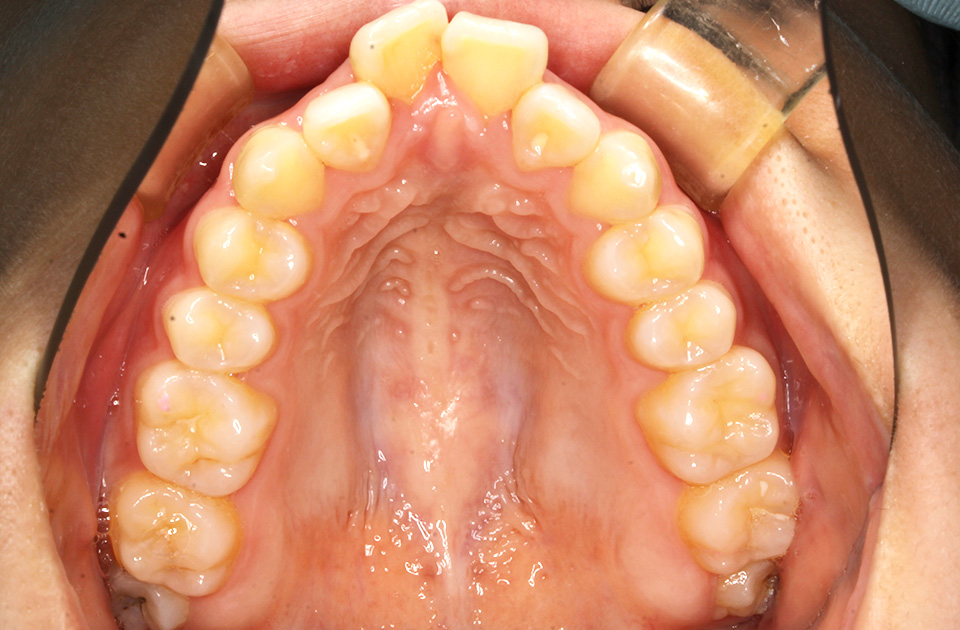

矯正前 上顎

矯正後 上顎

主訴 前歯で物が咬めない、歯並びの凸凹、出っ歯を治したい

治療法 上下顎マルチブラケット装置、歯科矯正用アンカースクリュー

抜歯の有無 上顎左右側第一小臼歯、下顎左右側第二小臼歯